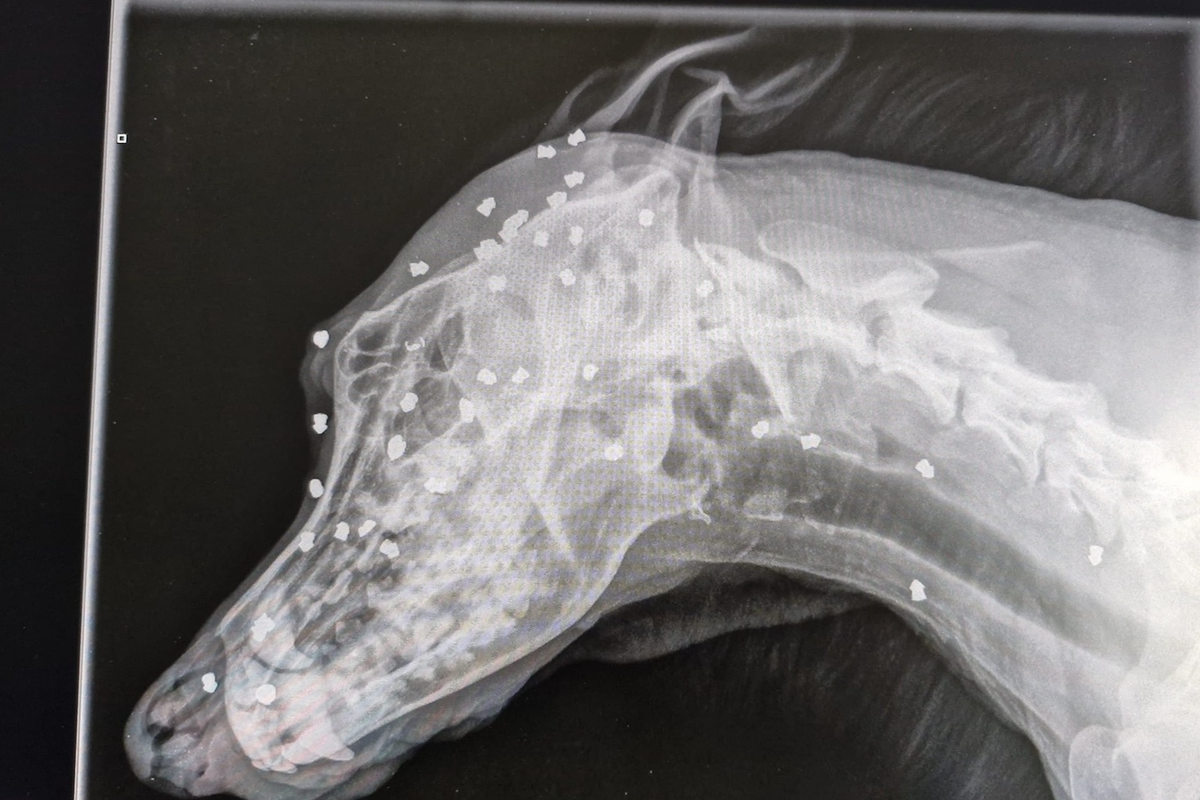

An X-ray found between 40 and 50 pellets lodged in the dog, deep in its bones and muscles. The body scan image shows the pellets scattered throughout the dog’s forehead and neck.

“Our vet examined the dog thoroughly and took x-rays,” the animal shelter workers said in a statement post on Facebook. “Unbelievable what they showed.